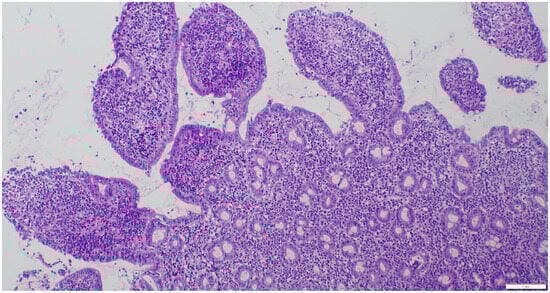

2.3. Sample Collection and Histopathologic Assessment

3.2. Results of Histology/IHC and Clonality Testing